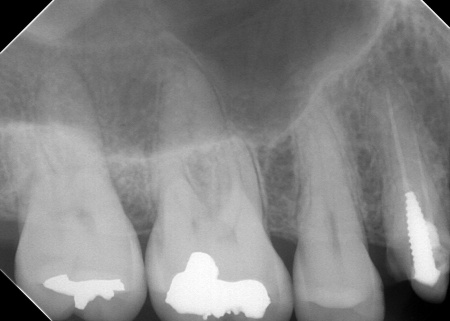

レントゲン撮影をして詳しく検査したところ、複数の小さな虫歯が見られました。

また右上奥歯には、歯根の先に炎症が起きて膿が溜まる根尖性(こんせんせい)歯周炎が認められます。

②根尖性歯周炎を発症している右上奥歯には、歯根内の細菌を除去して薬を詰める「根管治療」を実施し、歯の温存を図ります。患者様は、以前同じ歯に根管治療を行った経験があったため「再根管治療」となります。

次に、右上奥歯の古い材料(以前の根管治療に使用したもの)を除去し、歯根内部の洗浄と消毒をしてから新しい材料で密封し、被せ物を作製して装着しました。